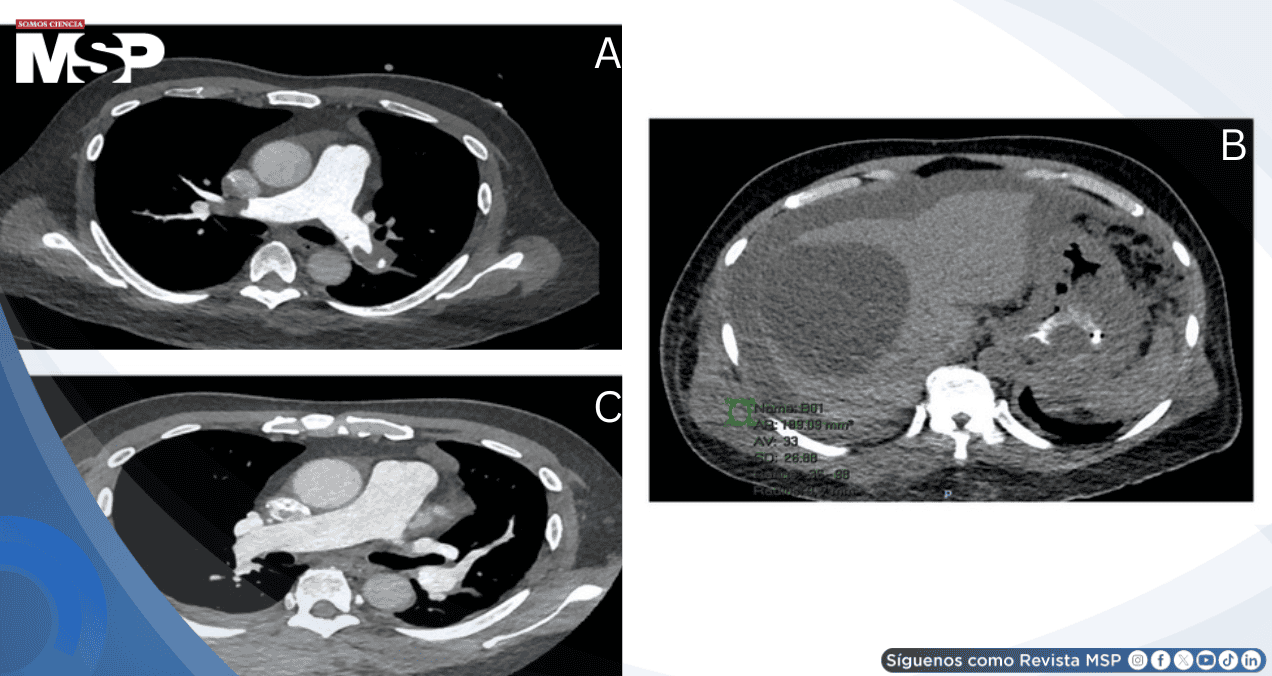

Se inició enoxaparina, se suspendió la eritropoyetina y fue trasladado a cuidados progresivos. Al segundo día presentó desaturación hasta 88% e hipotensión de 80/60 mmHg requiriendo oxígeno suplementario y norepinefrina. La angiotomografía pulmonar confirmó embolia pulmonar en silla de montar.

Se cambió a heparina no fraccionada y se trasladó a cuidados intensivos donde recibió trombólisis con alteplasa 100 mg. El ecocardiograma de control mostró mejoría con normalización de la presión de arteria pulmonar de 52.4 a 26.5 mmHg y mejora del cambio fraccional del área de 17% a 28.4%. Se reinició enoxaparina, pero desarrolló hematoma inter e intramuscular en región superior derecha de la espalda, por lo que se suspendió temporalmente la anticoagulación.

Al quinto día se colocó filtro en vena cava inferior por la trombosis extensa de extremidades inferiores. La angiotomografía de control mostró regresión moderada a marcada de los émbolos pulmonares bilaterales. Pudo completar su ciclo 5 de quimioterapia y fue dado de alta al día 15 con enoxaparina 0.6 ml subcutánea dos veces al día, dado que su puntuación de Khorana era 3, indicando alto riesgo tromboembólico.